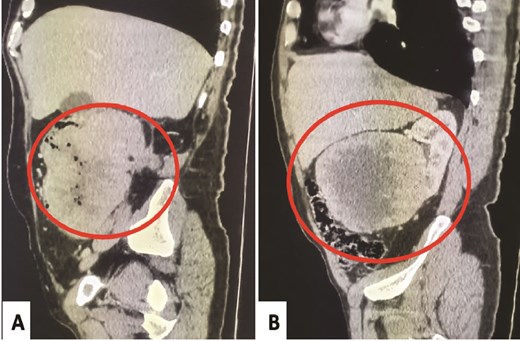

A 58-year-old male presented to the emergency department of Sheikh Khalifa International University Hospital for management of stercoral peritonitis. His surgical history included right nephrectomy 4 months earlier for lower polar kidney tumor diagnosed as pT4 CRCC, ISUP grade-4 with extensive tumor necrosis and sarcomatoid-rhabdoid changes (65%), and extensive. The abdominal CT-scan objectified a heterogeneous colon tumor without renal recurrence (Fig. 1A). Moreover, a second examination of the first abdominal CT-scan realized before the nephrectomy confirmed the presence of a localized heterogenous right renal mass pushing the ascending colon without any infiltration (Fig. 1B). Urgently, the patient underwent a right hemicolectomy with segment-VI hepatectomy.

Abdominal CT-scan post-nephrectomy: Heterogeneous colonic tumor without renal recurrence (A). Initial abdominal CT-scan: Right renal mass pushing the ascending colon without any evidence of invasion (B).